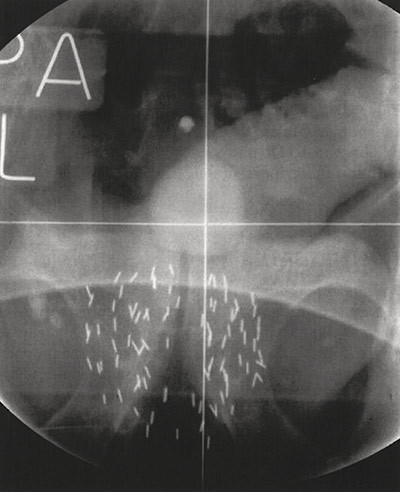

Low-dose-rate brachytherapy, or internal radiation, is a high-technology therapeutic procedure which allows the deposition of very high cumulative short-range radiation doses in the prostate (‘brachy’ is Greek for short), while the radiation dose that is deposited externally is considerably reduced. The radiation dose from the iodine seeds is gradually deposited in the prostate over a period of about two months (Fig. 2).

Figure 2  Radiological scan of the pelvis after low-dose-rate brachytherapy. Multiple radioactive iodine seeds are implanted…

Figure 2 Radiological scan of the pelvis after low-dose-rate brachytherapy. Multiple radioactive iodine seeds are implanted permanently in the prostate gland. The patient is catheterised and the balloon in the bladder above the symphysis is clearly visible. Photo: Bereich Interdisziplinäre Brachytherapie, Universitätsklinikum Schleswig-Holstein, Campus Lübeck. Published with the permission of Dr György Kovács